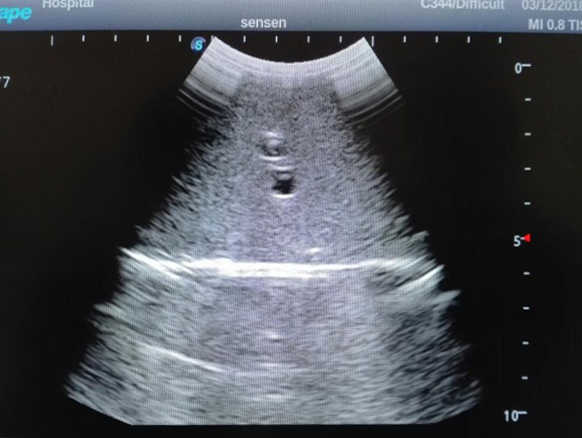

2)  High quality ultrasound image with clear structures like gallbladder, liver, intestines, arteries and veins etc.

3)  Compatible with all types of clinical ultrasound machines

4)  ltrasound gallbladder pathologies like cholecystitis, gallstone and polypoid degeneration

5)  Normal & pathological ultrasound live and intestine models inside